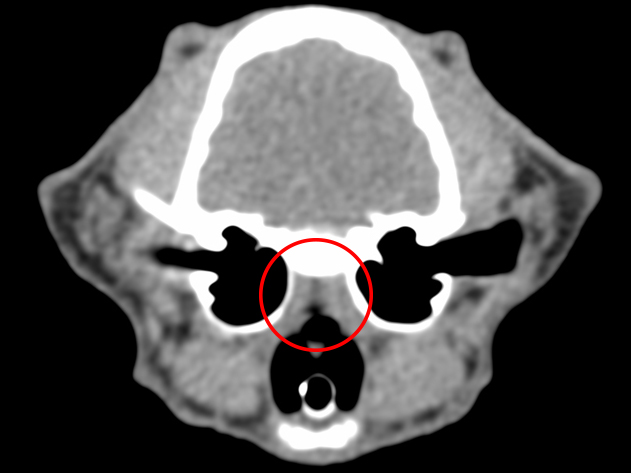

CT検査:赤丸が狭窄部位